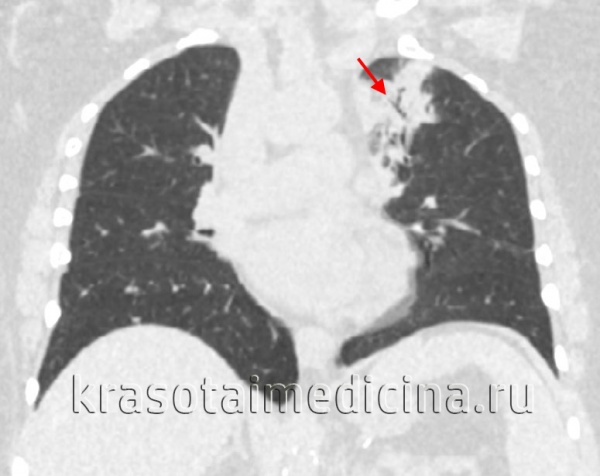

(Справа) На корональной КТ без КУ определяется классическая постпервичная картина туберкулеза с наличием множественных центрилобулярных очагов в обоих легких и очагов в виде «дерева в почках». Картина соответствует эндобронхиальной диссеминации заболевания. У пациентов с иммунодефицитом часто наблюдается кавитация.

• Разветвленные структуры и очаги в виде «дерева в почках»:

о Микобактериальные, бактериальные, вирусные инфекции

о Разбросанные очаги с поражением всех долей легких (высокая вероятность Mycobacterium avium-intracellulare)

• Постпервичная картина ТБ и классические/некавернозные НТМБ: преимущественно поражение верхних долей легких:

о Неоднородные участки консолидации: сегментарные, долевые, мультифокальные

о Кавитация (45%)

о Эндобронхиальная диссеминация: очаги в виде «дерева в почках», центрилобулярные (2-4 мм) и ацинарные, дольковые участки консолидации